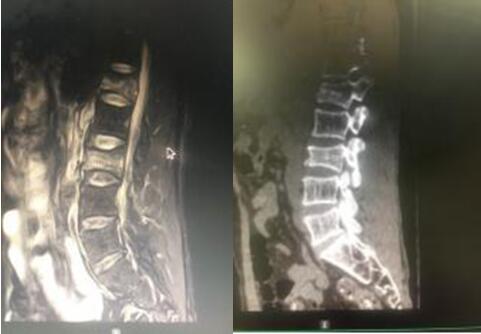

7月9日,經(jīng)與患者及其家屬充分溝通后,在脊柱外科蘇光輝主任、汪向東副主任帶領(lǐng)下順利進(jìn)行了經(jīng)皮跨傷椎長(zhǎng)節(jié)段后路內(nèi)固定手術(shù)治療腰椎骨折。術(shù)后傷口小、出血量極小約50ml,術(shù)后1周即可下地行走,患者及其家屬對(duì)手術(shù)效果相當(dāng)滿意。

術(shù)后